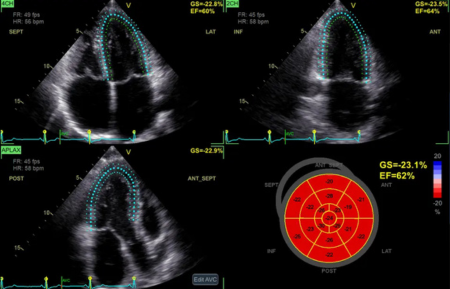

AutoEF модуль автоматического определения фракции выброса левого желудочка

AFI опция автоматической недопплеровской оценки деформации миокарда левого желудочка